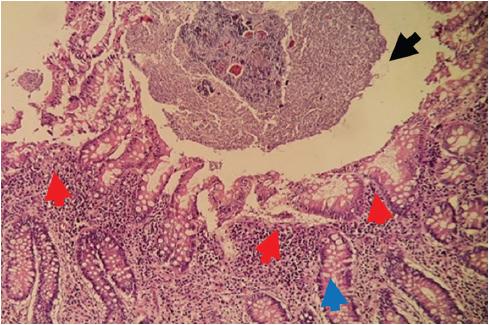

Exploratory laparotomy was performed, finding cone-shaped surgical mesh eroding the parietal peritoneum, with adhesions to the omentum, cecum, and cecal appendix (Fig. 2). A 10x1 cm erythematous, edematous, and hyperemic cecal appendix, with the presence of appendicolith at the tip. Finally, an appendectomy was performed by dismantling the surgical mesh cone and closure of the peritoneum. The mesh was placed using the Lichtenstein technique in its entirety. The patient evolved favorably and was discharged 24 h after surgery. Pathology revealed cecal appendix with reactive lymphatic hyperplasia and passive congestion (Figs. 3-5).

Figure 2 Surgical mesh (black arrow) eroding parietal peritoneum (green arrow), cecal appendix (red arrow), and mesoappendix (blue arrow).